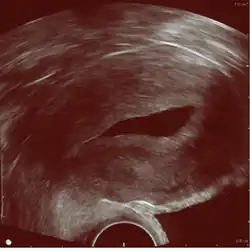

Sonohysterography using a balloon catheter (seen in the middle of the image)